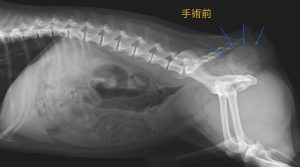

今回は、会陰ヘルニアについてです。会陰ヘルニアは、直腸周りの筋肉が萎縮して骨盤腔内の臓器が肛門周囲の皮下に変位する疾患で、犬や猫のみならず、人でも発症して外科的整復が必要となる疾患です。原因として、未去勢(男性ホルモン)、腹圧の上昇、外傷などが挙げられます。私が獣医になりたての頃は、未去勢のワンちゃんが多かったせいか、よく診る病気の一つでした。ここ最近は予防医療が浸透し、減少傾向だと思います。症状は排便困難が最も多く、その他に排尿困難、消化器症状などが挙げられます。

今回治療させていただいたワンちゃんは、「日によって便秘になり、便が出ても形が細くおかしい」との主訴で来院されました。肛門の右側の皮下に、石のように硬くなったテニスボール大の宿便を認めました。本人は便が出づらい以外はとっても元気なのですが、 硬くなった便が肛門を塞いでおり、想像するだけでもとても辛そうです。

一般的な治療法は、手術による骨盤隔膜の再建と去勢手術になります。自分の筋肉や靭帯などを用いた整復法や、人工物のメッシュを用いた整復法などがあり、重症度や筋肉がどれくらい残っているかによって方法を検討します。

このワンちゃんは、自分の筋肉がそこまで弱っていなかったため、最もシンプルな筋肉と靭帯を縫合する方法を選択して、無事に整復することができました。